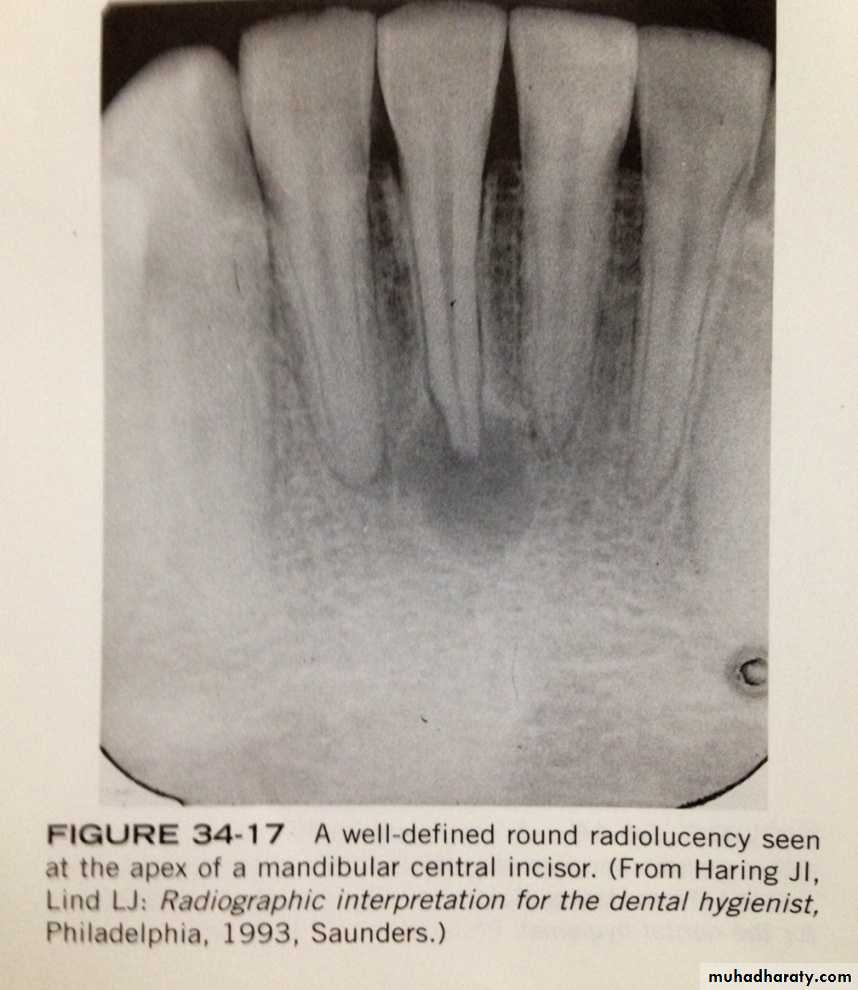

periapical granulomas, cysts, and abscesses are common periapical radiolucencies that can be seen on dental radiographs. these lesions cannot be diagnosed by there radiographic appearences alone;instead diagnosis is based on the clinical features and radiographic and microscopic appearences. Because its impossible to distinguish between these three periapical lesions based on there radiographic appearence, the dental radiographer should refer to these lesions simply as "periapical radiolucencies".

on a dental radiograph, a periapical granuloma is initially seen as widened periodontal ligament space at the root apex. with time, the widened periodontal ligament space enlarges and appears as a round or ovoid radiolucency.PERIAPICAL GRANULOMA

on dental radiograph the typical periapical cyst appear as a round or ovoid radiolucencyPERIAPICAL ABSCESS